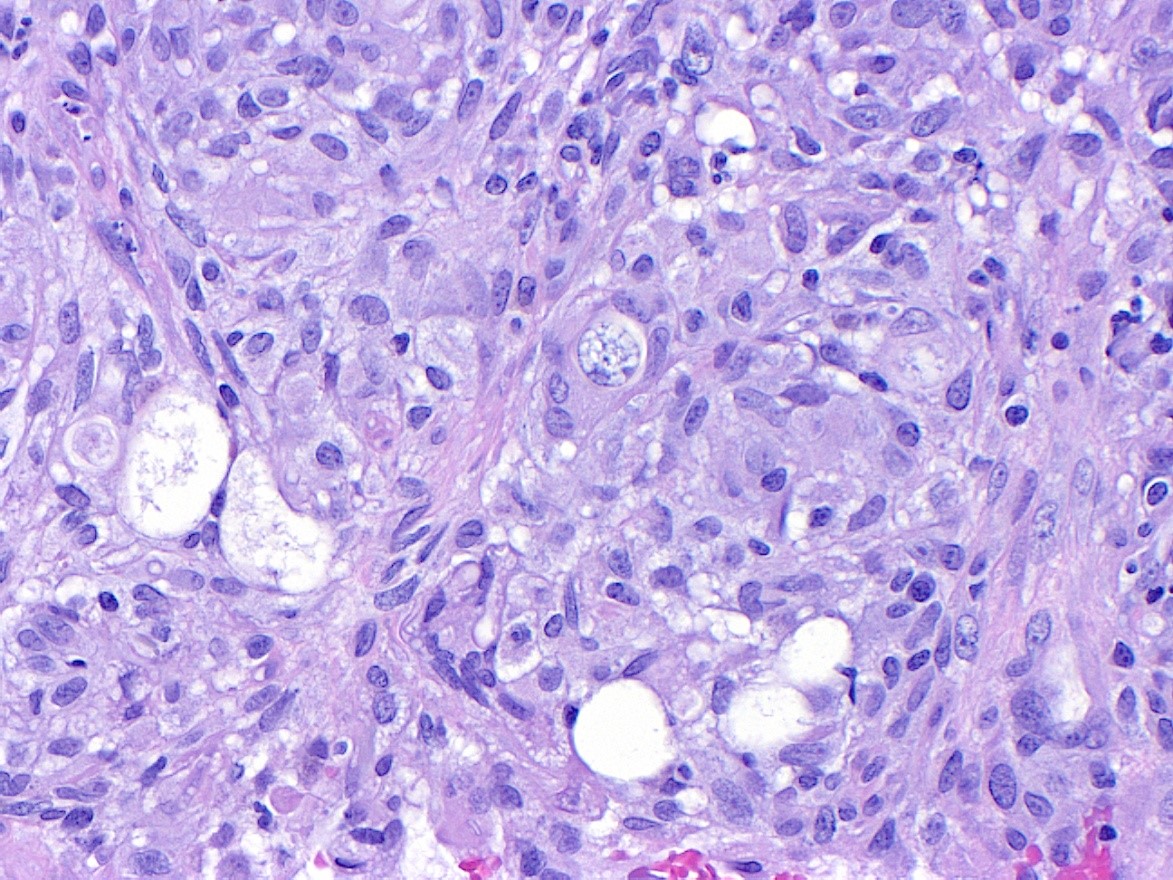

Figure 6. H&E, 10x magnification |

Figure 7. H&E, 20x magnification.